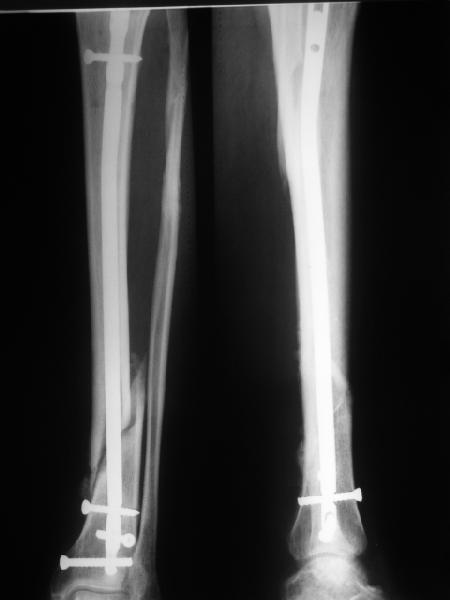

>СА> По Вашему намного реально стало лучше?

По-моему, стало так, как должно быть.

Здесь проблема не в идеальности репозиции, а в запасе усталостной прочности. Срастаться там может небыстро, диастазы довольно большие.

И когда еще и отломок короткий, и отверстие совсем рядом, это может привести к перелому стержня. За последние годы у нас было несколько пациентов, оперированных в других учреждениях с

подобным положением отломков, с такими переломами гвздей. И сейчас переделать куда как проще и легче, чем иметь дело со сломанным гвоздем.

По крайней мере, при нынешнем положении фиксатора стал меньше риск того, что до сращения гвоздь сломается.